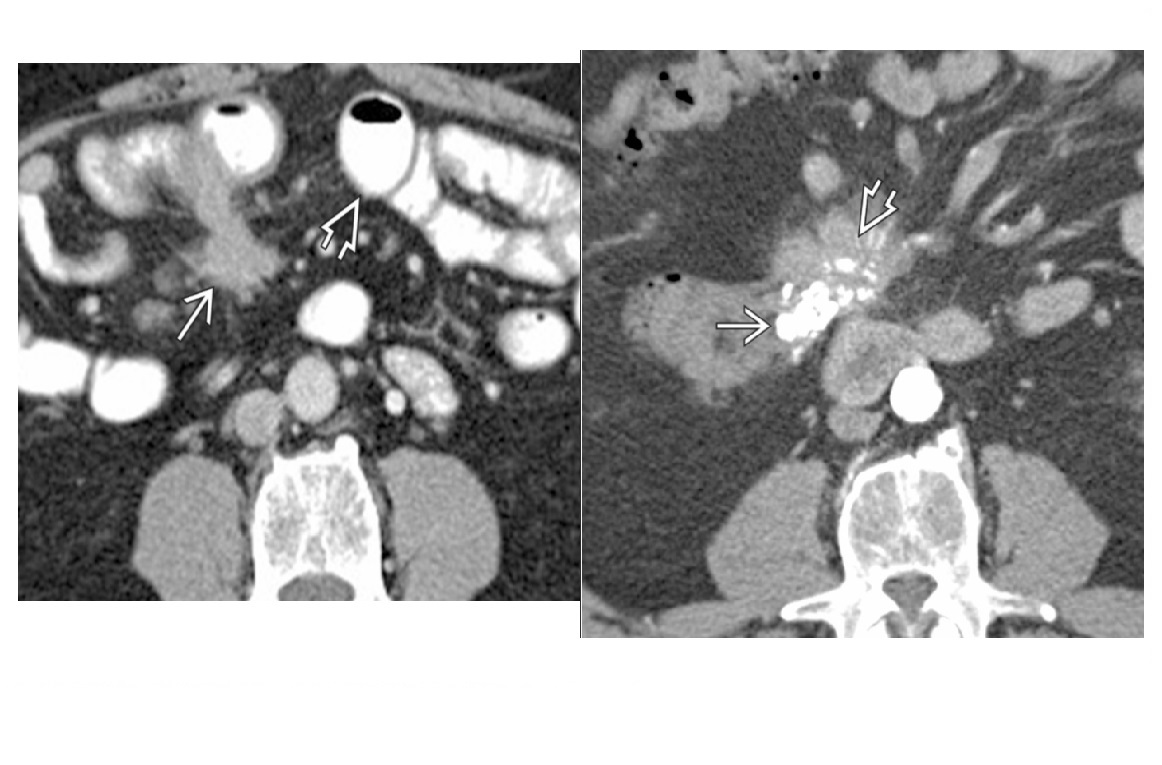

Carcinoid

spiculated mesenteric mass with calcification/ desmoplastic reaction

Tethering of SB loops

90% arise in terminal ileum/appendix

Hyper-vascular liver mets - Carcinoid syndrome

111I- Octreotide scans (1st - highest sensitivity)

or 123I-MIBG (for 10% dont take up octreotide)

for Dx and staging

Big centres use gallium PET

Assocaited with MEN 1 or MEN 2a

DDX

Sclerosing mesenteritis/ mesenteric pannicultuis

- FAT HALO sign - Mass envelop vessels, but preservation of fat around vessels

- usually jejunal small bowel mesentery